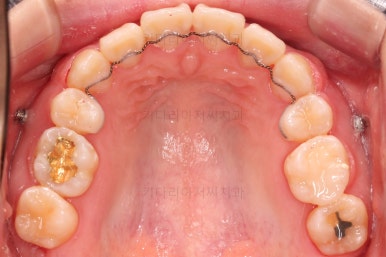

밀고 당기기와 디테일을 더 정리한 뒤 부산무턱교정치과 마무리를 하게 됩니다.

교합, 과개교합 모두 좋아졌고요.

발치 공간도 깔끔하게 닫히고 종료했습니다.